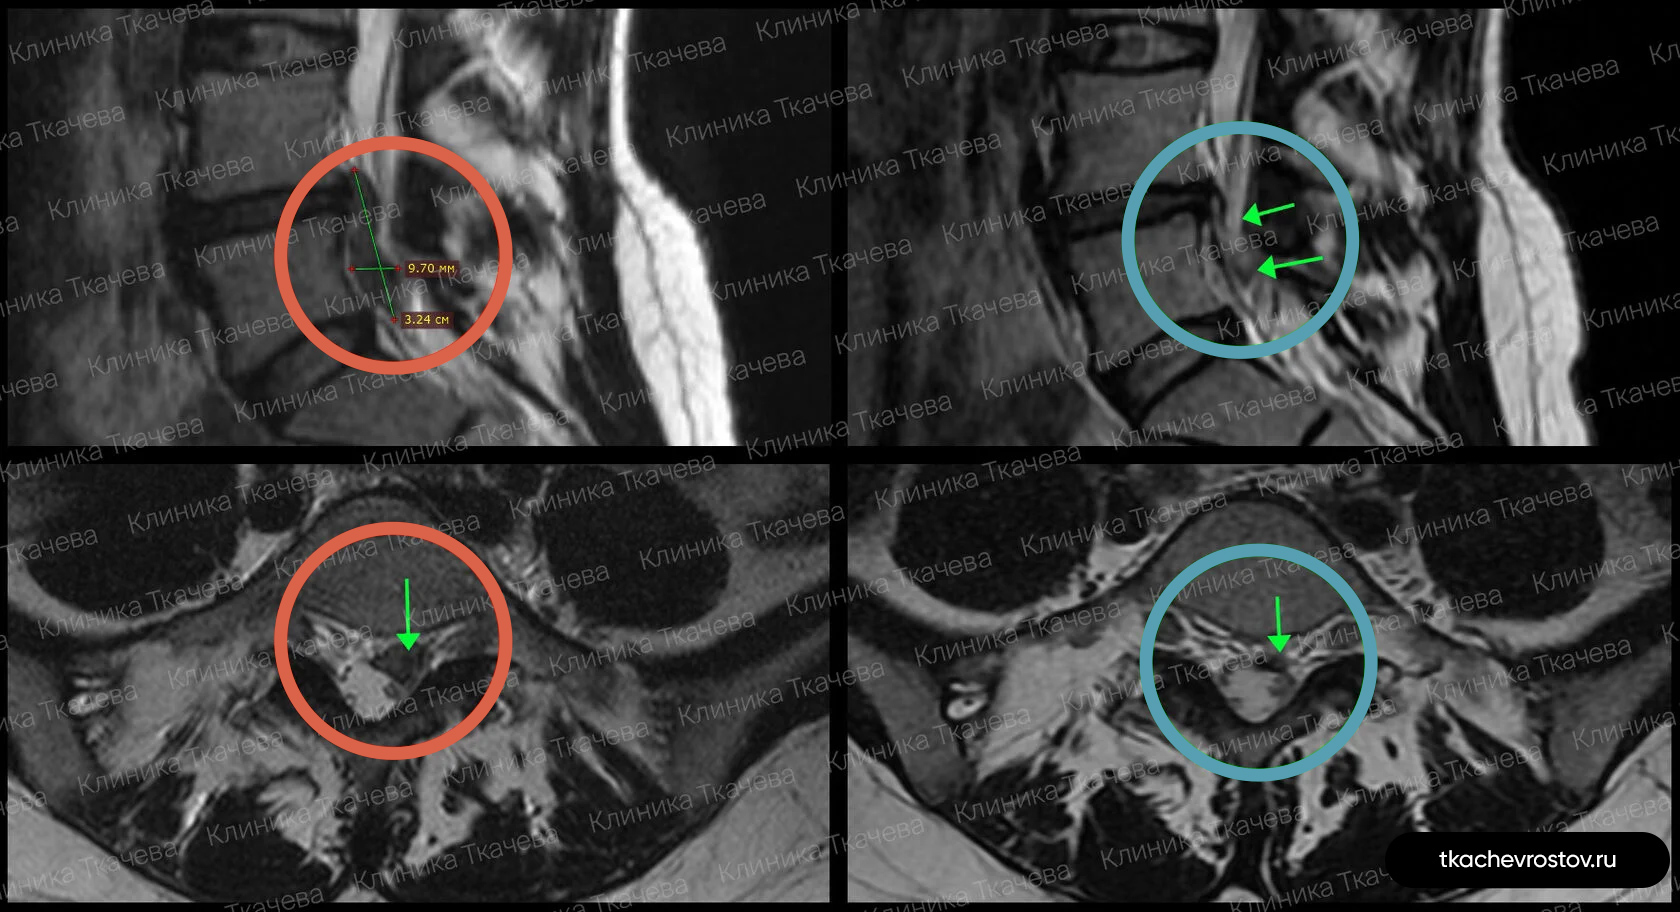

Женщина. Грыжа в сегменте L4-L5 9 мм х 2 см. Невролог направлял на операцию, нейрохирург пугал отказом всех возможных систем жизнеобеспечения.

ДО:

- Боль в спине

- Онемение в левой ноге

- Снижение бытовой и социальной активности

ПОСЛЕ 1 курса:

✓ Наступила полная резорбция грыжи

✓ Наступило улучшения общего состояния.

ПОСЛЕ 2 курса:

✓ На 2022 всё стабильно.

Лечение грыжи заняло 5 месяцев. Было проведено 2 курса лечения.